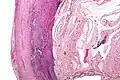

Even for clinically certain appendicitis, routine histopathology examination of appendectomy specimens is of value for identifying unsuspected pathologies requiring further postoperative management.[69] Notably, appendix cancer is found incidentally in about 1% of appendectomy specimens.[70]

Pathology diagnosis of appendicitis can be made by detecting a neutrophilic infiltrate of the muscularis propria.

Periappendicitis (inflammation of tissues around the appendix) is often found in conjunction with other abdominal pathology.[71]

Micrograph of appendicitis and periappendicitis. H&E stain